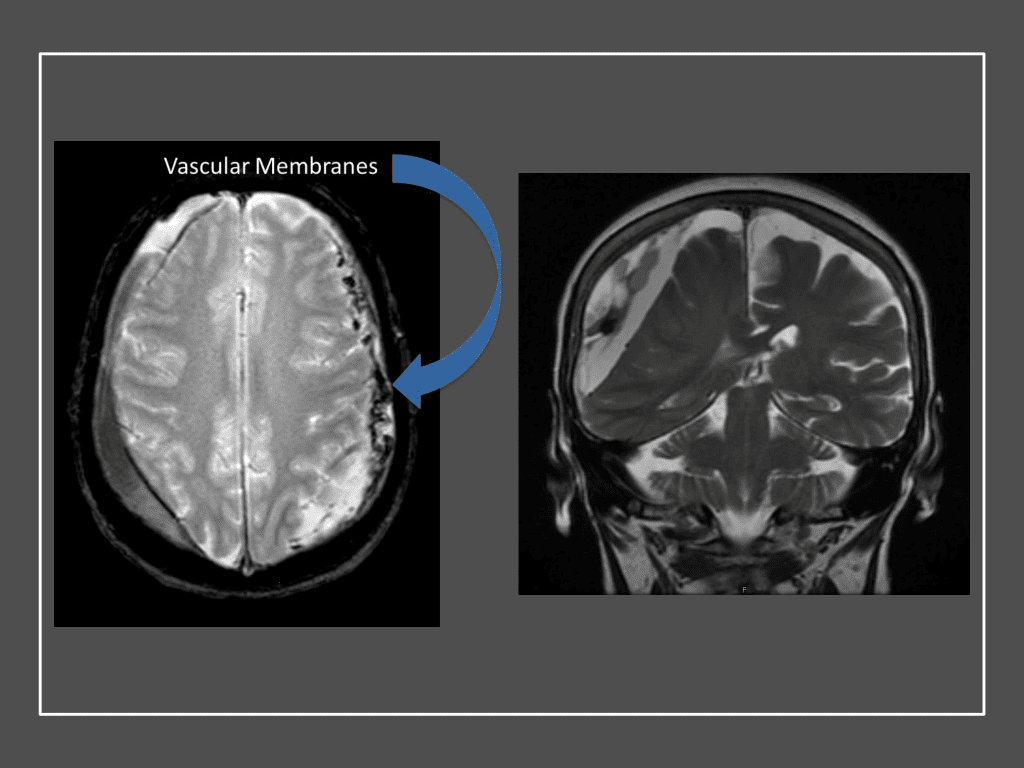

The patient agreed to receive minimally invasive treatment with Bilateral Middle Meningeal Artery Embolization, a new approach to promote resorption of chronic and subacute subdural hematomas in patients that are not improving with conservative measures or have contra-indications to surgical evacuation. Selective catheterization of the Middle Meningeal Artery is followed by transarterial embolization of the territory and inflammatory membranes that are felt to be secreting serosanguinous proteinaceous exceeding the capacity for resorption. MMA embolization was performed bilaterally in this patient. (Figure 2. A and B)

Figure 2. A) Initial right ECA angiogram ; B) Post MMA Embolization; C) Selective Embolization Of Middle Meningeal Artery Membranes using PVA particles (arrows).